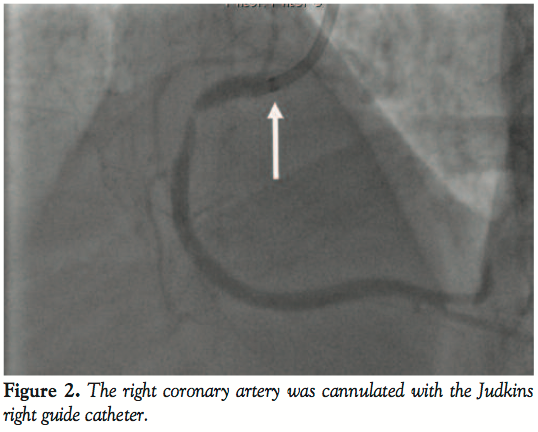

Coronary angiogram revealed a significantly tight stenosis of 95% in the proximal segment of the right coronary artery (RCA) with the other vessels having no significant disease (Figure 1). We treated the culprit vessel percutaneously by cannulating the RCA with a 7 Fr Judkins right guiding catheter (Figure 2) and using a 0.014” Galeo wire (Biotronik) to cross the lesion. The lesion was predilated with 3 mm x 10 mm Sprinter balloon (Medtronic) at 10 atm (Figure 3). However, just after withdrawing the balloon into the